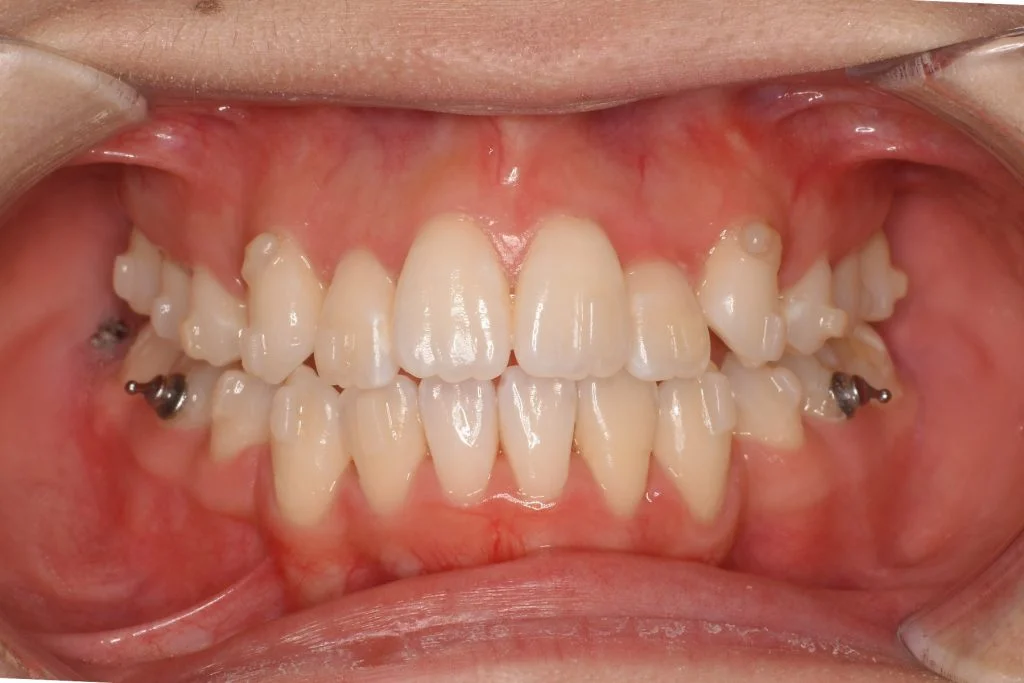

• 症例1-2治療後

1年経過時 大体1年で八重歯やガタガタは解消されます

Q.アタッチメント(歯の突起)やゴムかけは必要ですか?

A.基本的には必要です。八重歯は歯の回転や上下の動きが絡みやすいので、治療中の見た目は多少損ないますが、結果優先で補助装置を併用します。補助装置を使用することで、最短でかつ正確に、きれいに仕上がります。